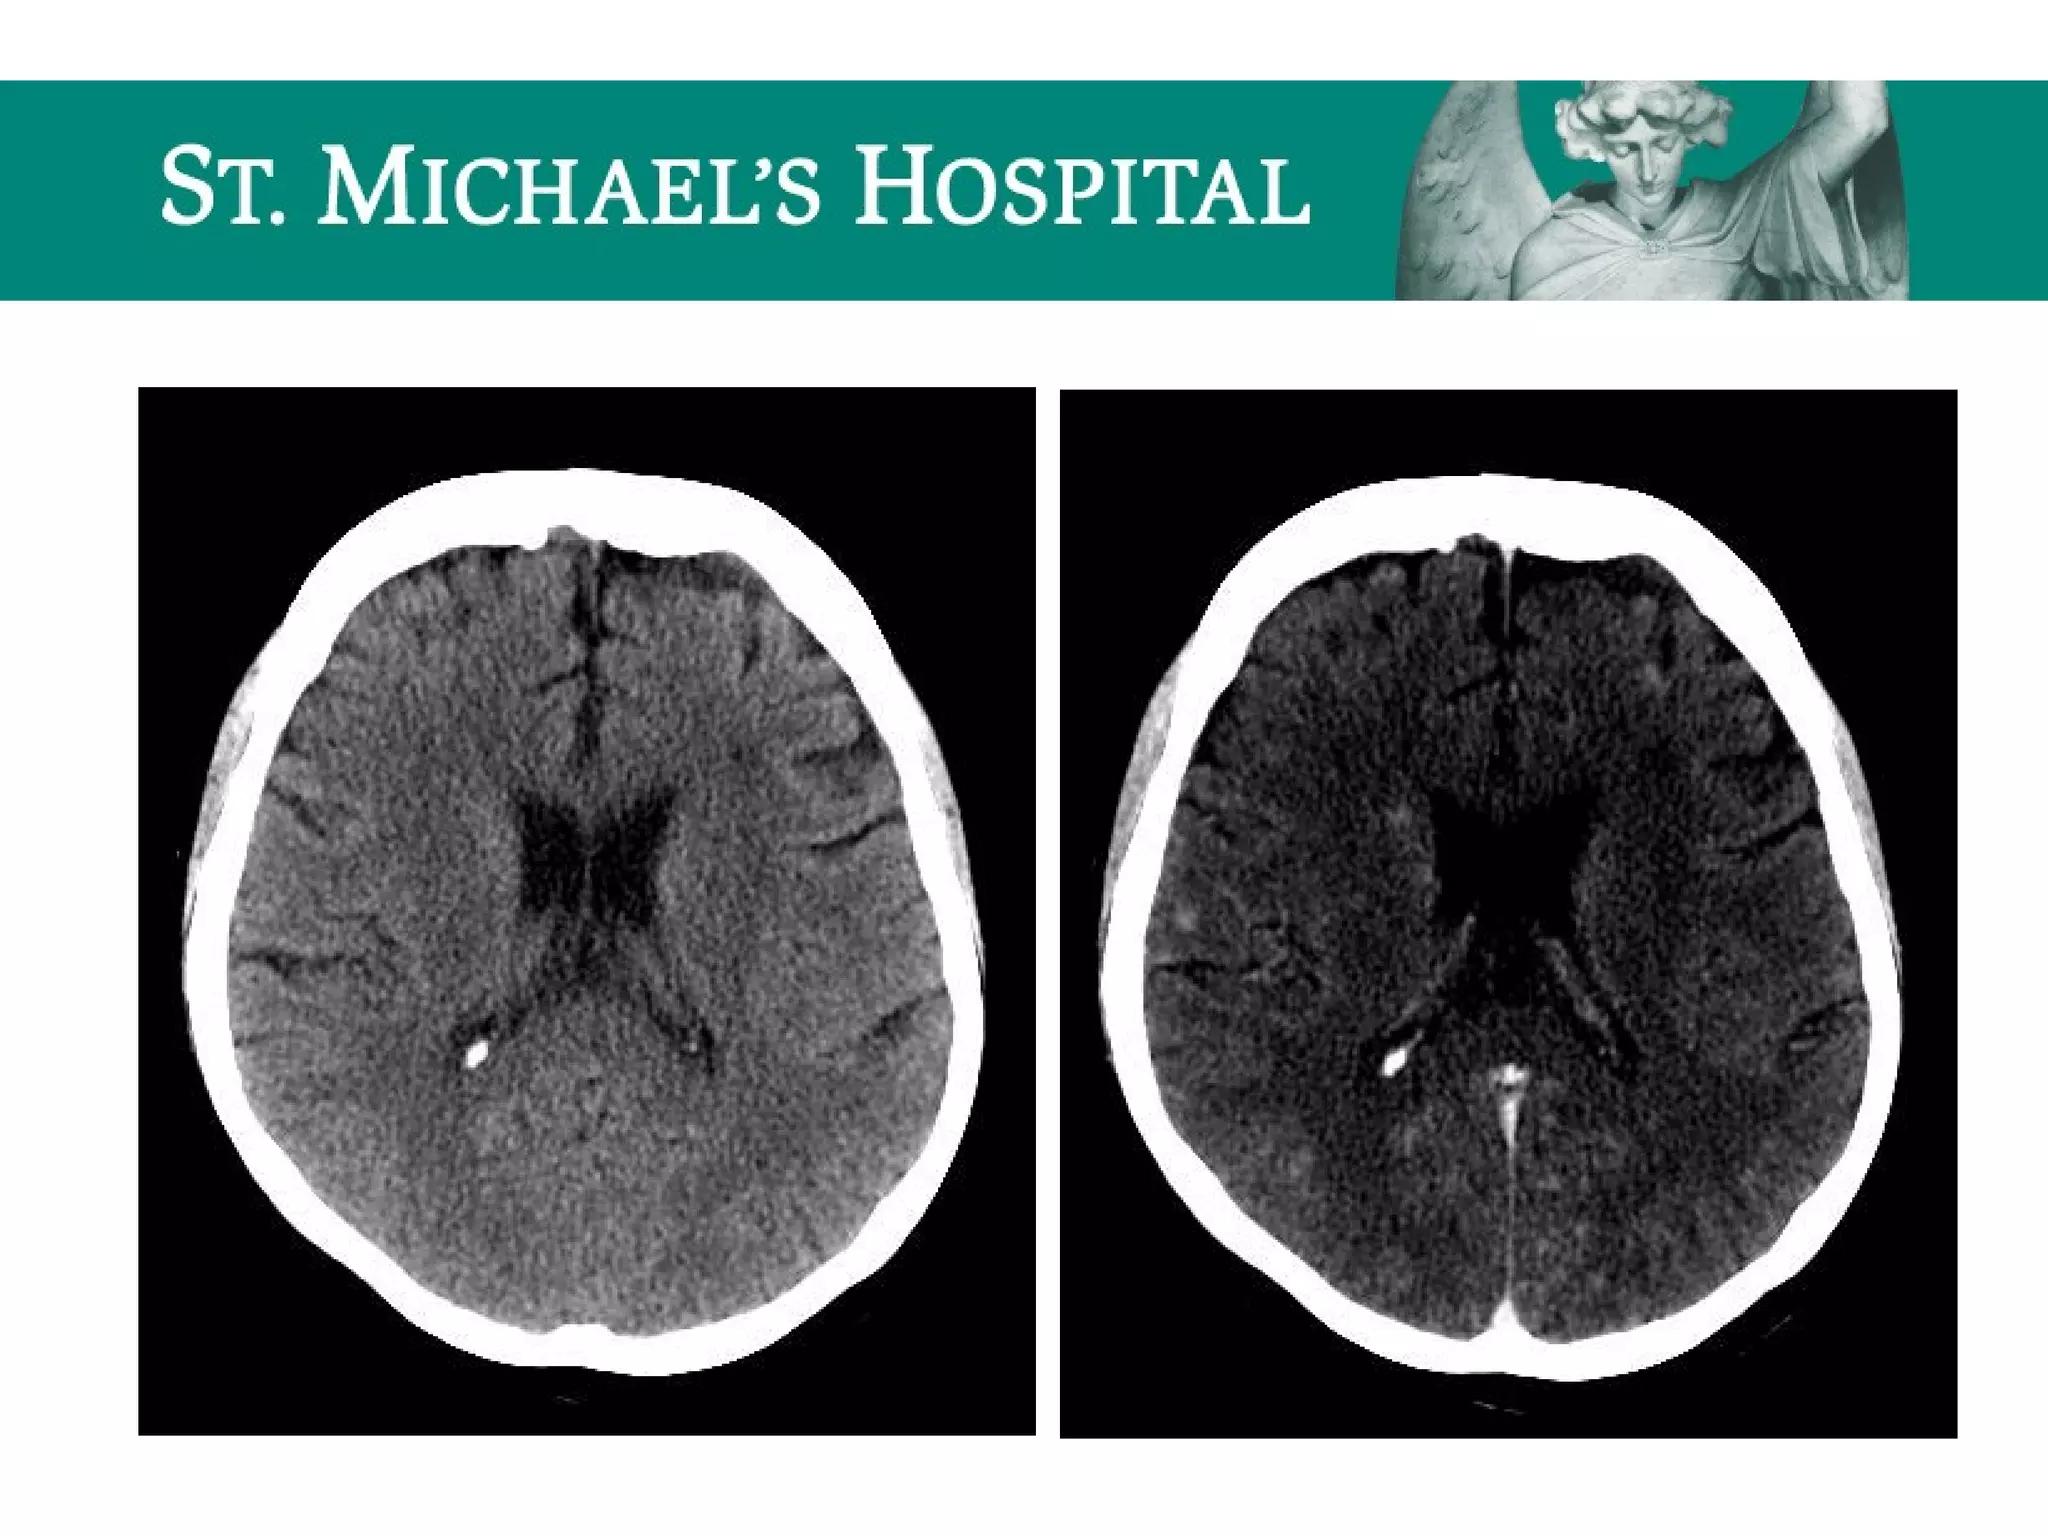

Global Cerebral Ischemia/Anoxic Brain

Injury

 Diffuse brain swelling/edema can result in:

 global loss of gray-white differentiation

 global sulcal/cisternal effacement

 pseudo-subarachnoid hemorrhage

 dense cerebellum

Communicating Hydrocephalus

 Blockage of CSF flow over the cerebral convexities/absorption at the arachnoid

granulations secondary to:

– SAH, meningeal mets, granulomatous meningitis

 Rapid CSF production

 eg. choroid plexus papilloma

 Radiological features:

 Symmetrical enlargement of the lateral, third and fourth ventricles

 Normal/effaced cerebral sulci

 Dilatation of subarachnoid cisterns

 Periventricular low attenuation  transependymal flow of CSF

Non-communicating Hydrocephalus

 Location of obstruction/causes:

 Lateral ventricles  ependymoma, meningioma

 Foramen of Monro  third ventricular colloid cyst

 Aqueduct of Sylvius  congenital aqueductal stenosis, IVH

 Fourth ventricle/foramen of Luschka and Magendie  congenital, tumour,

extrinsic compression

 Ventricular dilatation proximal to the level of obstruction

 Earliest indication may be dilatation of the temporal horns

 Progressive enlargement of the ventricular system which is disproportionate

to narrowed and effaced cortical sulci

 Periventricular low attenuation (transependymal CSF flow)